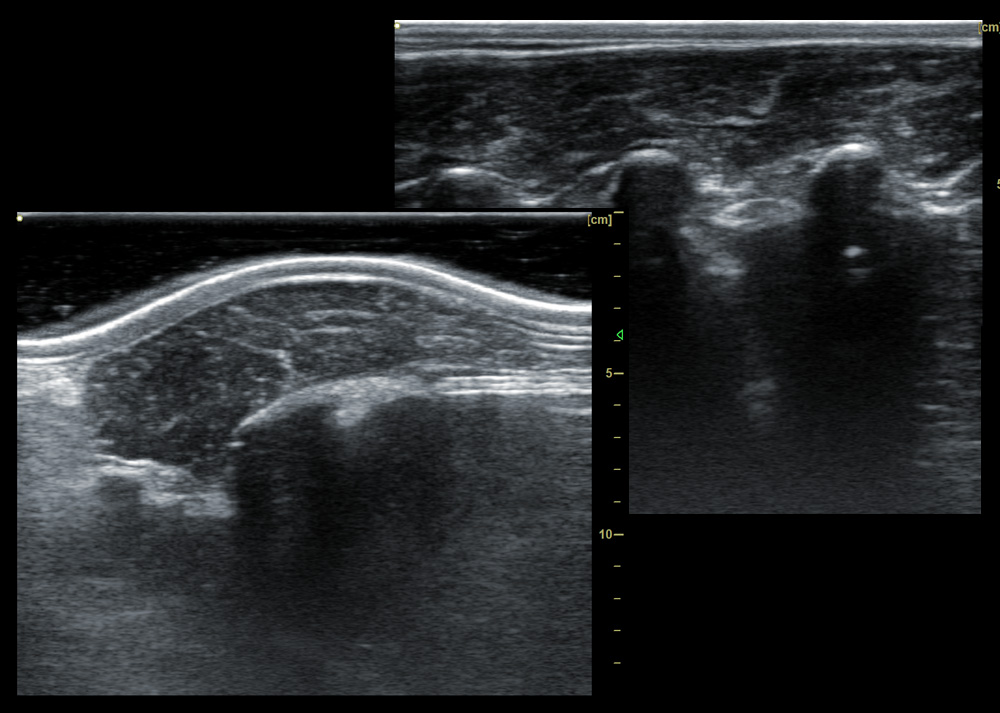

IV. Features of animal backfat eye muscle probe:

1. 18cm long professionally designed backfat eye muscle probe, which can fully test the backfat eye muscles of various animals

2. The probe scanning depth can reach 30cm, which can well present the eye muscles of large animals

3. High-frequency probe and high-quality Doppler color ultrasound images can well identify the measured muscle quality grade